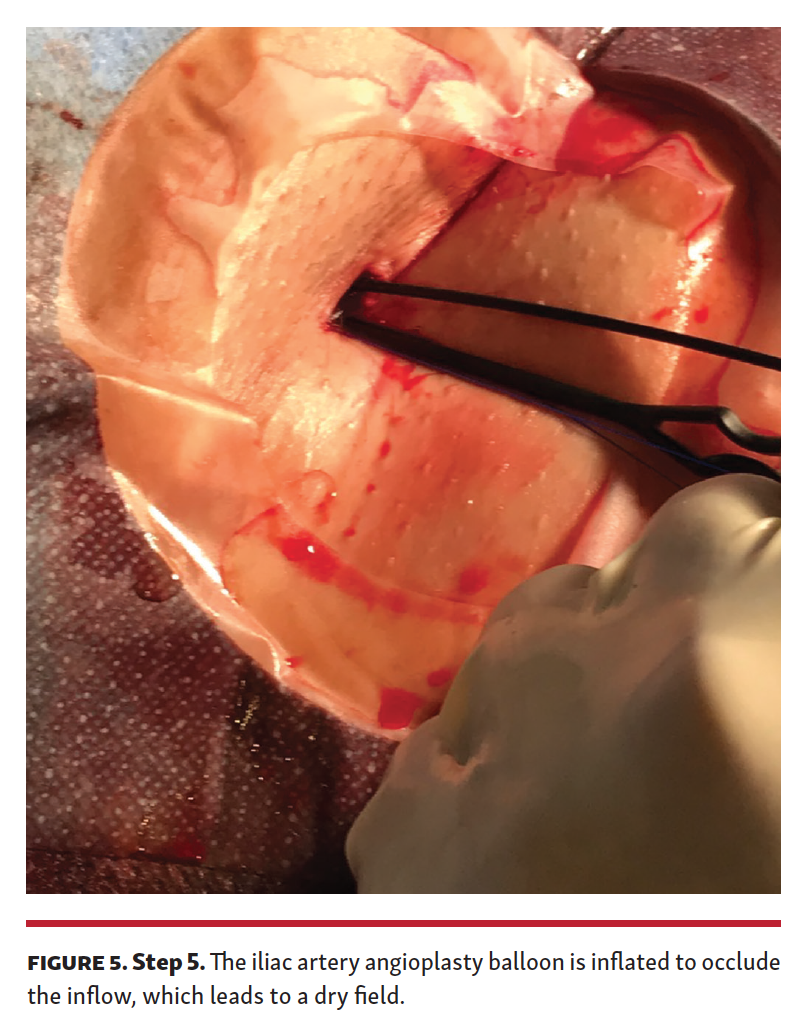

Step 5. The Proglide suture knot is gently pushed down, without tightening it, on the balloon shaft to avoid entrapment. The field should be dry without manual pressure, while the iliac balloon is inflated (Figure 5).